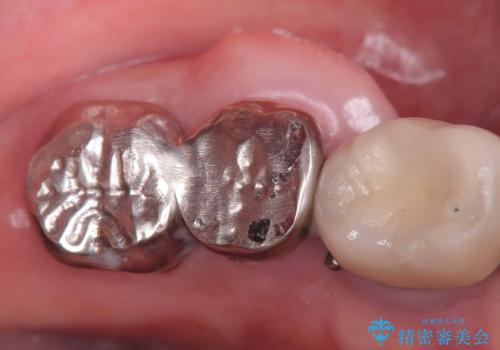

- 治療計画

- 「歯を咬むと痛い」を主訴に来院された患者様です。 CTを撮ると歯根が縦に真っ二つに割れている状態で、歯周ポケットも10㎜を超える状態でした。

歯の保存は困難と診断しインプラントで治療を行いました。1Dayインプラントの適応だったので、抜歯した当日にインプラントを埋入しました。